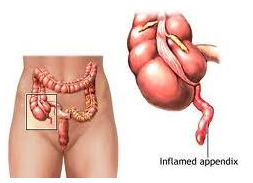

Para se tornar um Cirurgião Pediátrico, o médico precisa fazer dois anos de residência em Cirurgia Geral e mais três anos de residência em Cirurgia Pediátrica, onde verá as diferenças existentes no tratamento dispendidos a um adulto e a uma criança, ganhando habilidade no manuseio desses pacientes tão especiais. Normalmente as cirurgias são mais delicadas, realizadas sob anestesia geral e não necessitam de dormir no hospital (porém muitas delas podem ser realizadas em regime de Hospital Dia com internação que varia de 6 a 12 h). Casos cirúrgicos comuns em crianças são as hérnias inguinal e umbilical, cistos da região do pescoço como os branquiais e o tireoglosso, testículos que não estão situados na bolsa testicular, hipospádia e outras malformações do aparelho urinário, fimose, anquiloglossia (“língua presa”), tumores e doenças gastrointestinais.